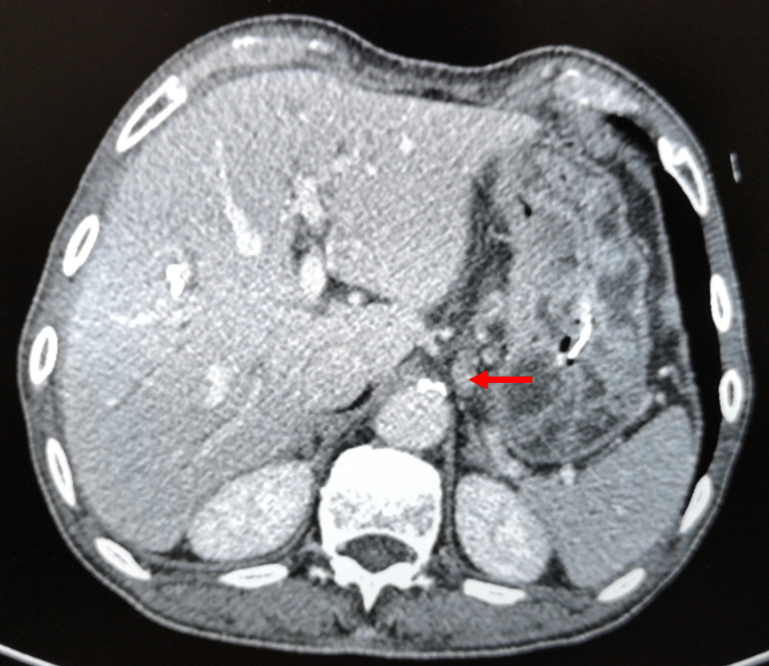

图1-1  2018-4-4  箭头为胃周肿大淋巴结

腹盆腔强化CT(2018-4-4):1、胃体及胃窦胃壁增厚,考虑胃癌;2、胃周、胃左动脉区及腹膜后多发肿大淋巴结,考虑转移;3、肝内胆管结石,肝内胆管轻度扩张;4、左肾囊肿,左肾上腺增厚,考虑增生;5、前列腺增生伴钙化;6、盆腔少量积液;7、两下肺实变索条,左侧胸腔少量积液。